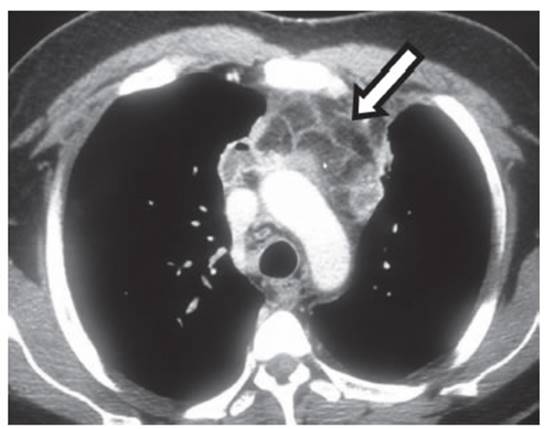

11 g/dl, Hcto 35,5%). La tomografía computarizada

contrastada de tórax, demostró presencia de edema y

líquido en los tejidos blandos superficiales anteriores infrahioideos del cuello por encima de la horquilla

esternal, y, en la fase contrastada trombosis de la vena yugular interna

izquierda (flecha Figura 1). A nivel de tórax ensanchamiento de